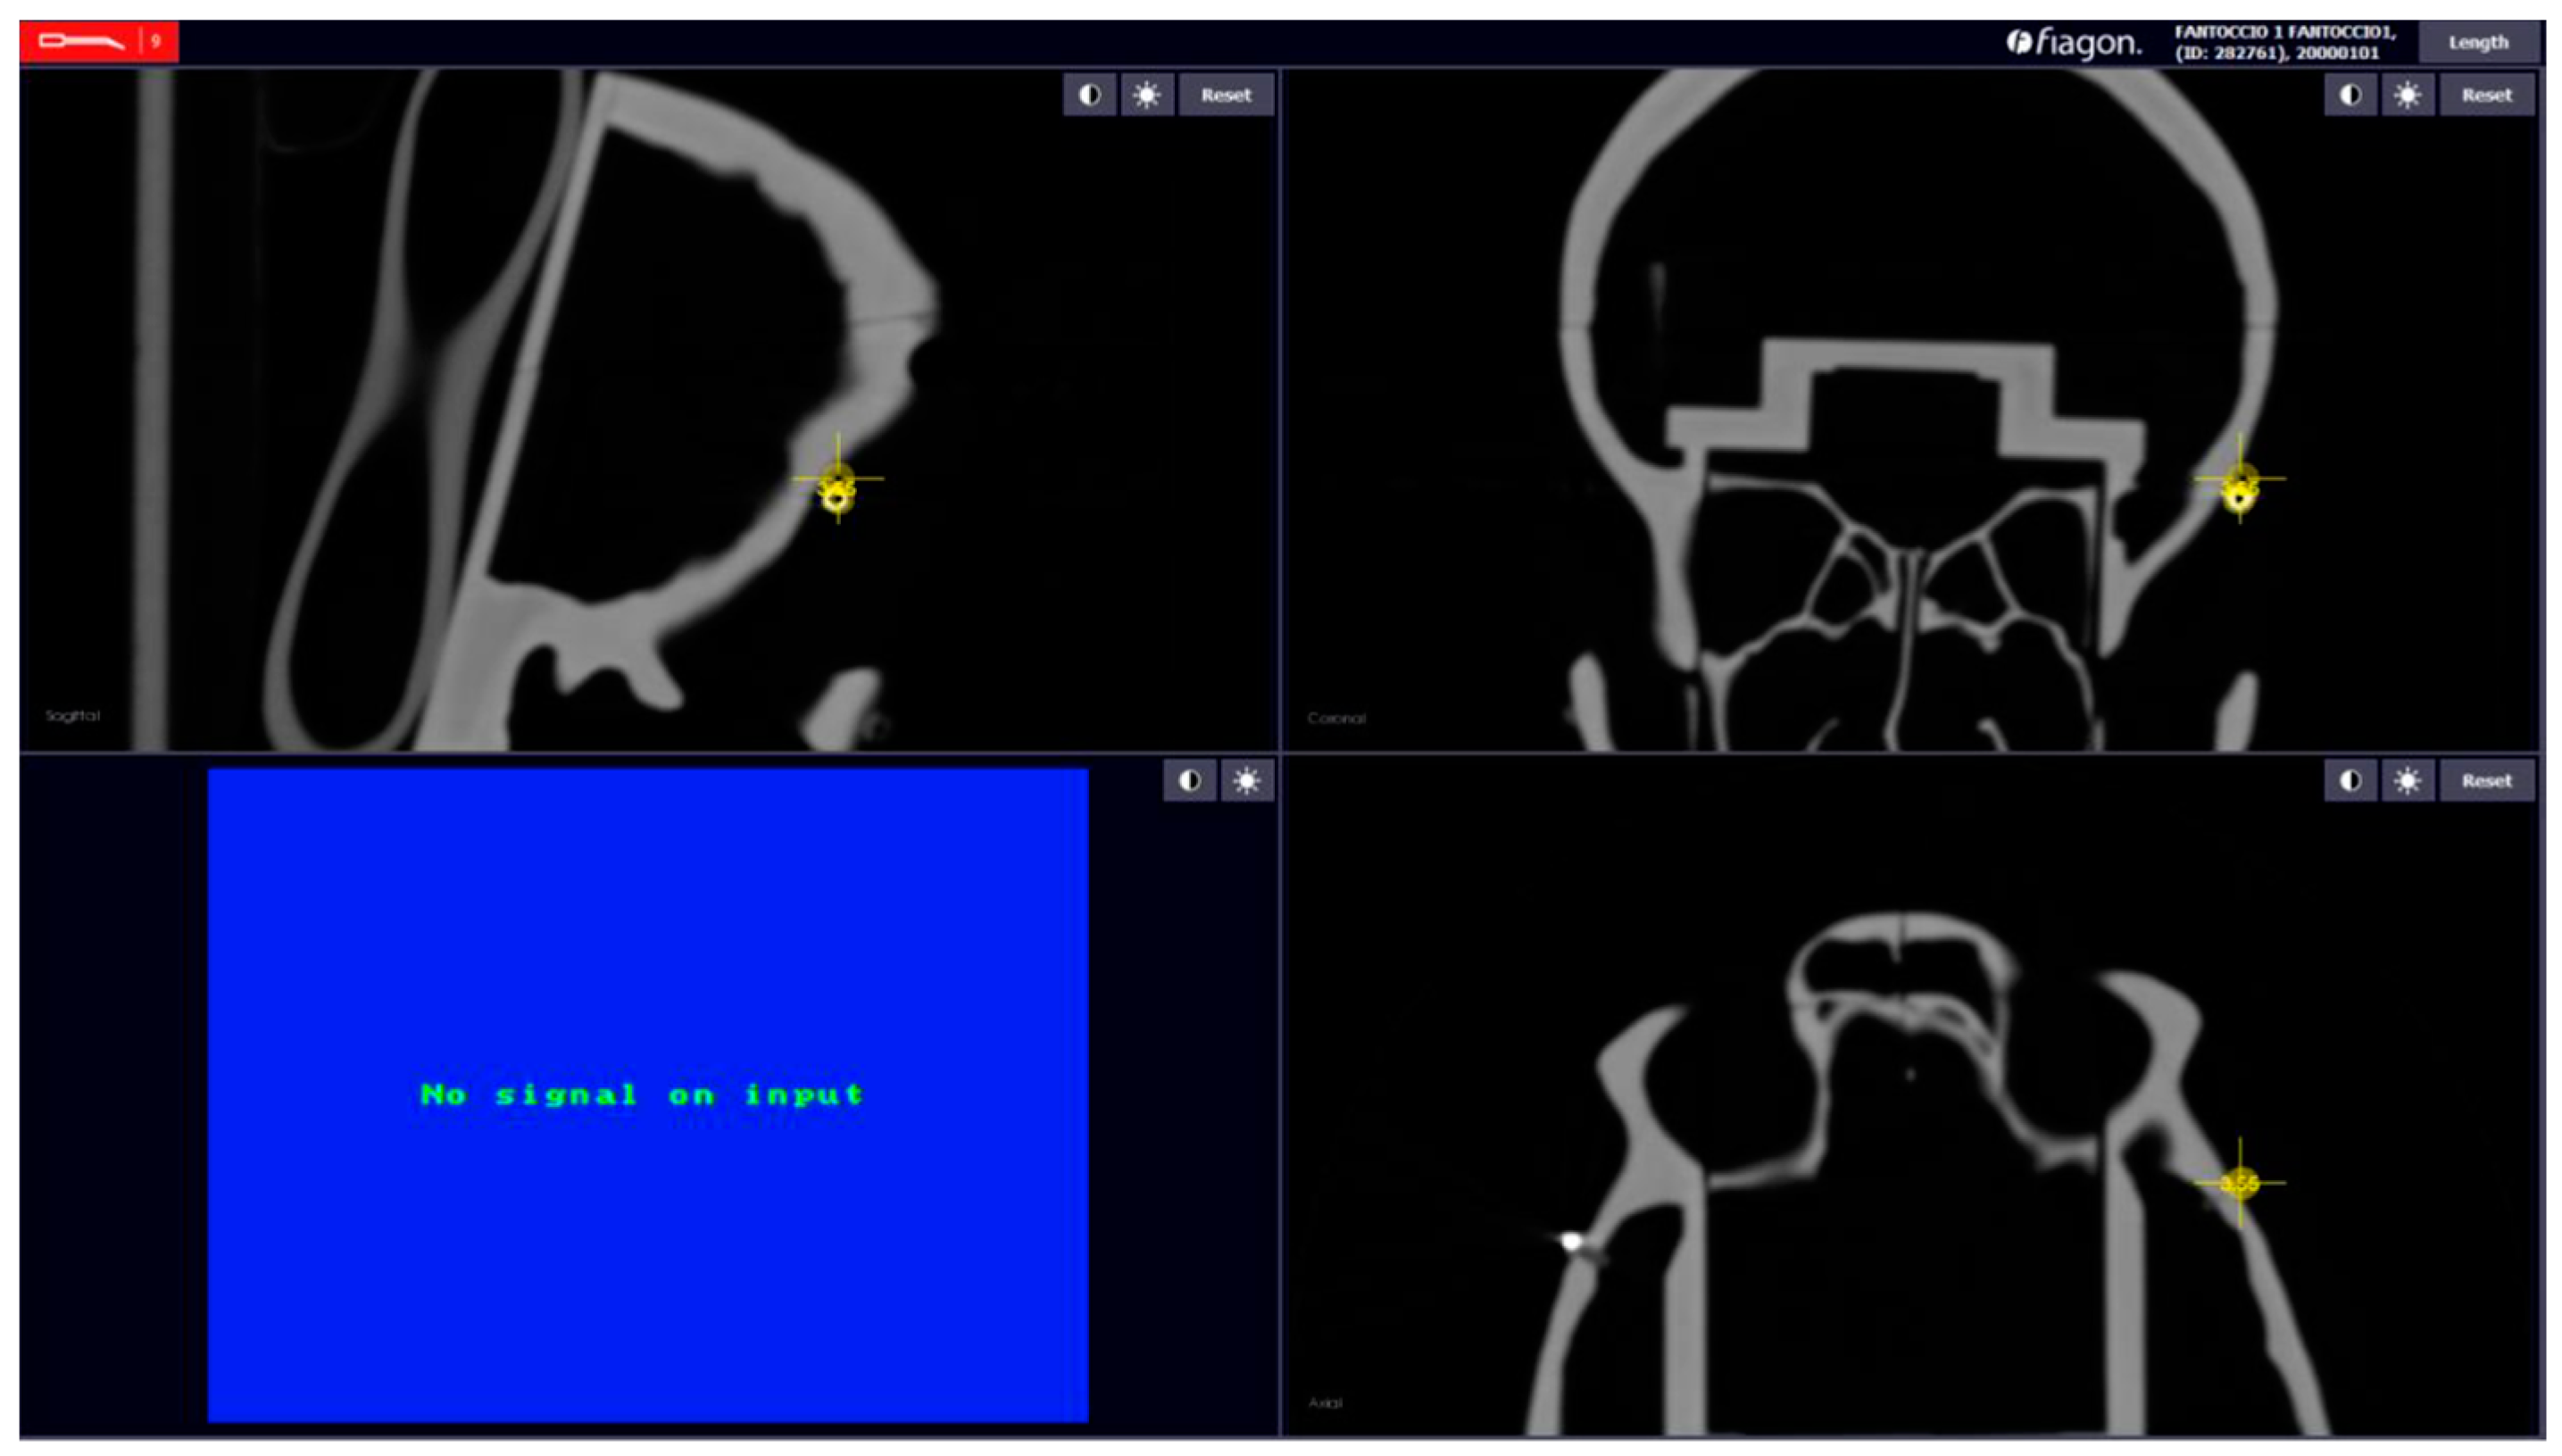

For each calibration, we evaluated the error of each sphere, between the position of the pointer and the position of the sphere in the CT, and calculated the measurements of each distance. After calibration, we used the command “Length”; it is present in the Fiagon Navigation Software (Version 3.7) module and allows you to measure the distance in millimeters. We used the spheres placed in different anatomical areas (Figure 8) to verify the accuracy of both sensors, the one placed on the front and the one placed on the created support.

2.6. Fiagon Measures

For each calibration performed, we calculated seven distances and the location error of each sphere. We calculated the length in millimeters between each sphere with the integrated software of the neuronavigator (Fiagon Navigation Software Version 3.7). The electromagnetic navigator allowed us to take screenshots of each measurement performed (Figure 9 and Figure 10).

Figure 9. Example: measure distance.

Figure 10. Error localization sphere nr.5.